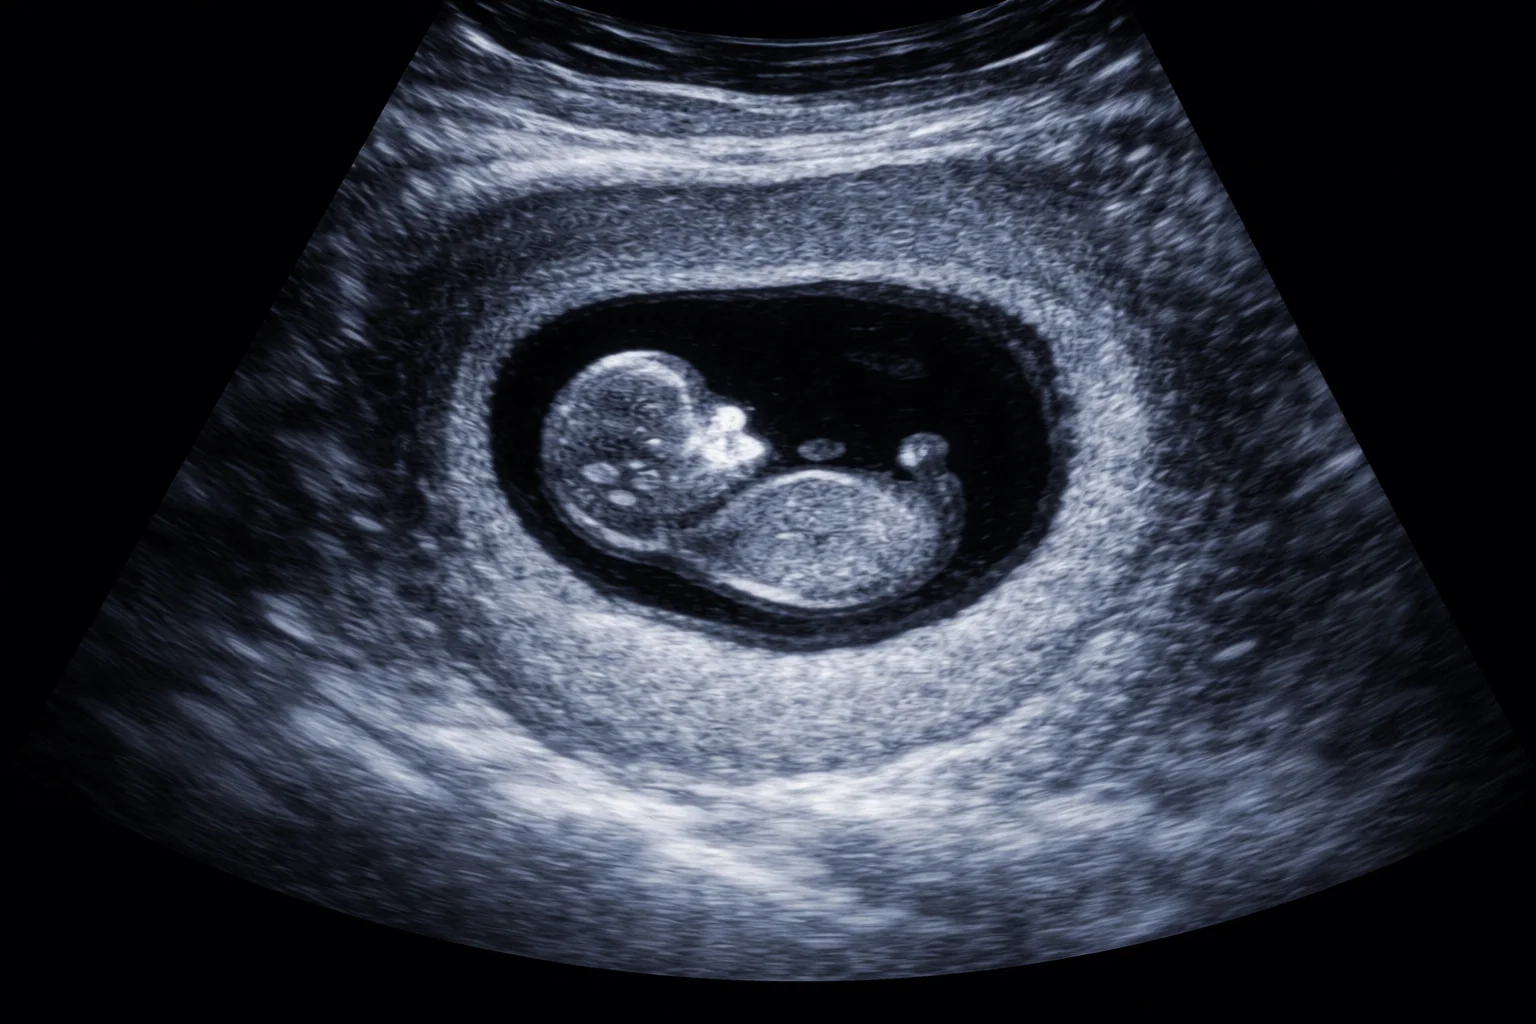

Hinzu kommt eine Entwicklung, die während der Corona-Zeit massiv vorangetrieben wurde: Die Abtreibungspille wird per Post verschickt – ohne ärztliche Untersuchung, ohne Ultraschall, ohne begleitende medizinische Betreuung. Die Frau bleibt allein, konfrontiert mit Schmerzen, Blutverlust, Angst und psychischer Überforderung. Verantwortung und Kontrolle werden ausgelagert, während das Risiko vollständig bei den Betroffenen verbleibt.